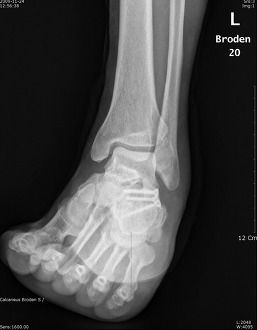

Broden view

촬영목적 : Subtalar joint의 골절시(comminuted fracture) 관절의 관련 여부를 관찰

촬영자세 : Supine 자세로 다리와 카세트 중앙은 일치하도록 하며,internal oblique자세에서 발목관절이 90˚ 굽힌상태를 유지하도록 발을등쪽으로 굽힌다.

중심선 :  cephalic 10˚ ,20˚, 30˚, 40˚ 로  Lateral malleolar에서 아래앞쪽으로 2~3Cm 떨어진지점에 입사한다

촬영Point : Subtalar Joint가 열려져 나타나며,10˚에서는 뒤쪽관절면의 뒷부분,20˚~30˚에서는 Sustentaculum(재거돌기)과 talus(거골)사이의 관절,40˚에서는 앞부분이 잘나타나야한다.